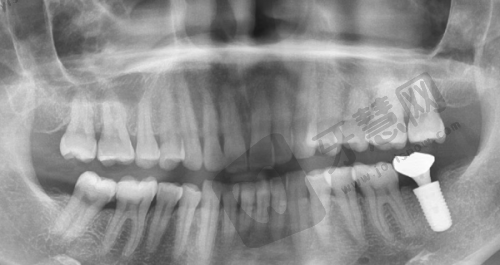

种植牙项目:设有种植牙中 心,主推ITI、BB、登腾、纽百特等多种品牌种植体,采用数字化种植技术、all - on - 4半全口种植等专精技术。数字化种植技术能让种植过程更加精细,减少手术创伤和时间;all - on - 4半全口种植技术为半口或全口缺牙患者提供了效率高的解决方案。

厦门翔安爱容口腔门诊部是经过卫生部门审批成立的正规口腔机构。厦门翔安新兴爱容口腔门诊部有限公司成立于2020年12月29日,统一社会信用代码为91350213MA35 aYBY2X,纳税人资质为一般纳税人。门诊部在运营过程中,严格遵守相关的医疗法规和行业标准,确保医疗服务的质量和安心。引进了智能化全景机、口扫仪、数字化牙科X光机、3D口腔扫描仪、超声骨刀等丰富的口腔设备,还设有无菌层流级种植手术室,内设专门的消毒区域,所有器械和设备都经过严格的消毒和灭菌处理,坚持一人一医一消毒,为患者提供安心、可靠的医疗环境。